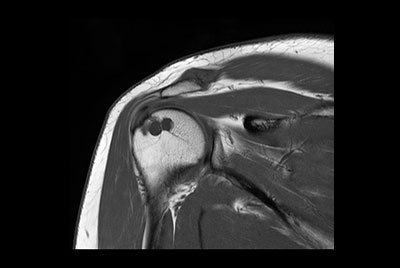

Shoulder with oncologic mass